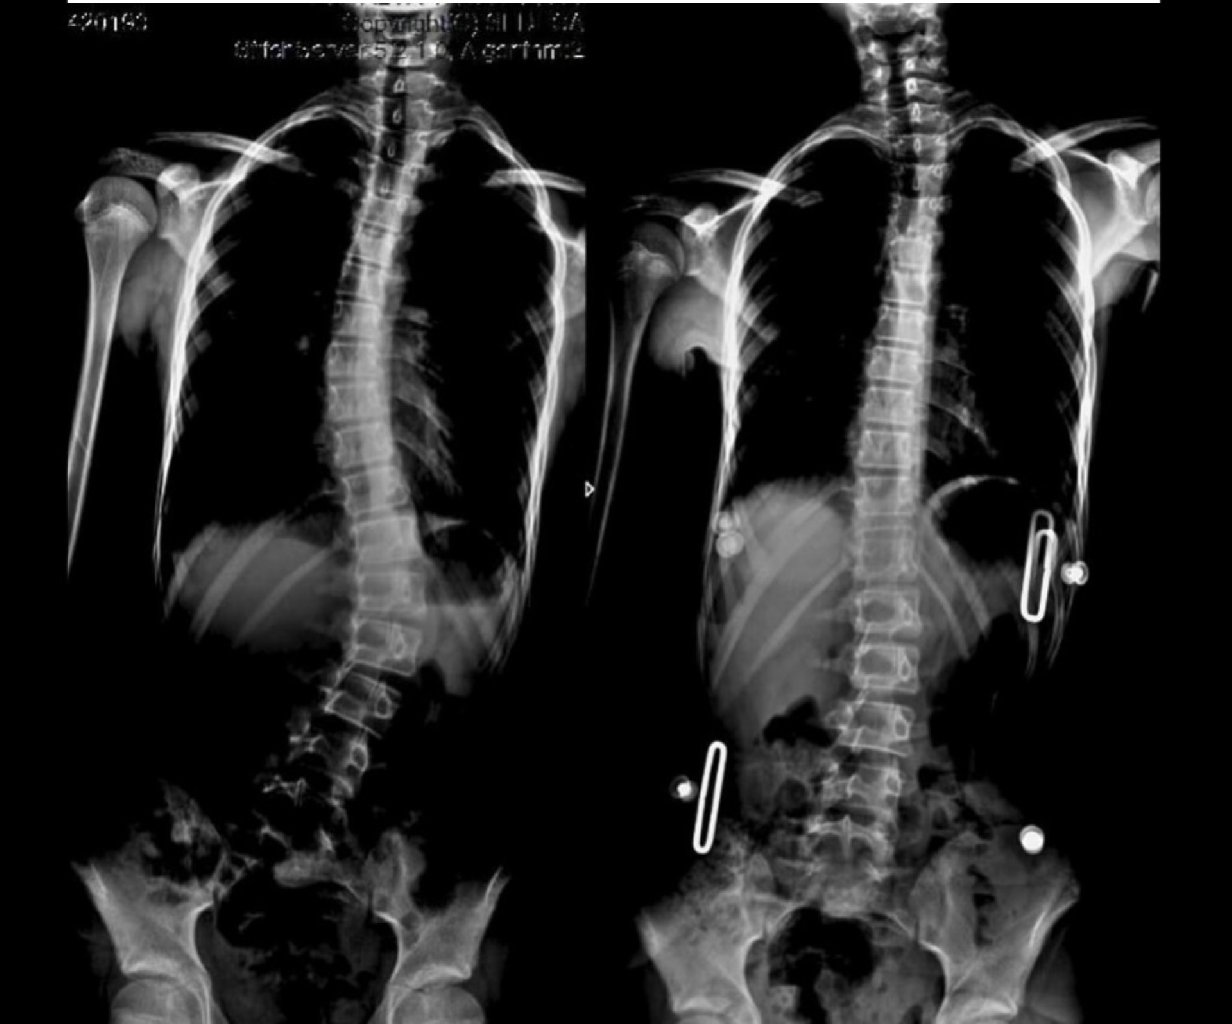

Yeniyetmə və Uşaqlarda Skoliozun Belirtiləri: Omurganın görünür əyriliyi Bir omuzun digərindən ...